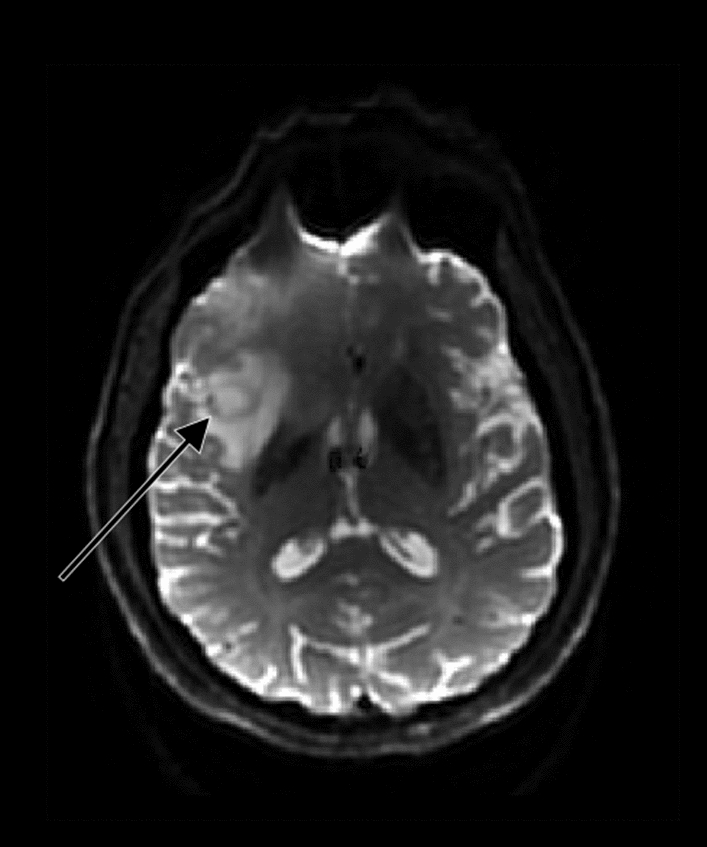

An alternative parameter to assess vascular proliferation within glioblastoma is regional cerebral blood flow (CBF). Relative CBF has shown a positive correlation with rCBV and microvascular density as an increase in CBF can be observed in high-grade gliomas; see Fig. 5 [51, 52]. Arterial spin labelling (ASL) is a non-invasive MR technique used to measure CBF and was found useful for non-invasive glioma grading [53]. By magnetically labelling the water molecules in arterial blood, which then flows into the brain, a tagged image of the brain can be acquired. Subtraction between labeled and control images creates images with signal weighted by cerebral perfusion that via a kinetic model can be quantified to generate images of CBF [54].

Fig. 5

ASL-CBF shows increased perfusion in a patient with a glioblastoma in the right frontotemporal lobe

Bild vergrößern